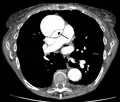

| Dissection of the descending part of the aorta (3), which starts from the left subclavian artery and extends to the abdominal aorta (4). The ascending aorta (1) and aortic arch (2) are not involved in this image. | |

CT with contrast demonstrating aneurysmal dilation and a dissection of the ascending aorta (type A Stanford)

Chest CT with descending (type B Stanford) aortic dissection (red circle)

Type A dissection with pericardial effusion as a result.